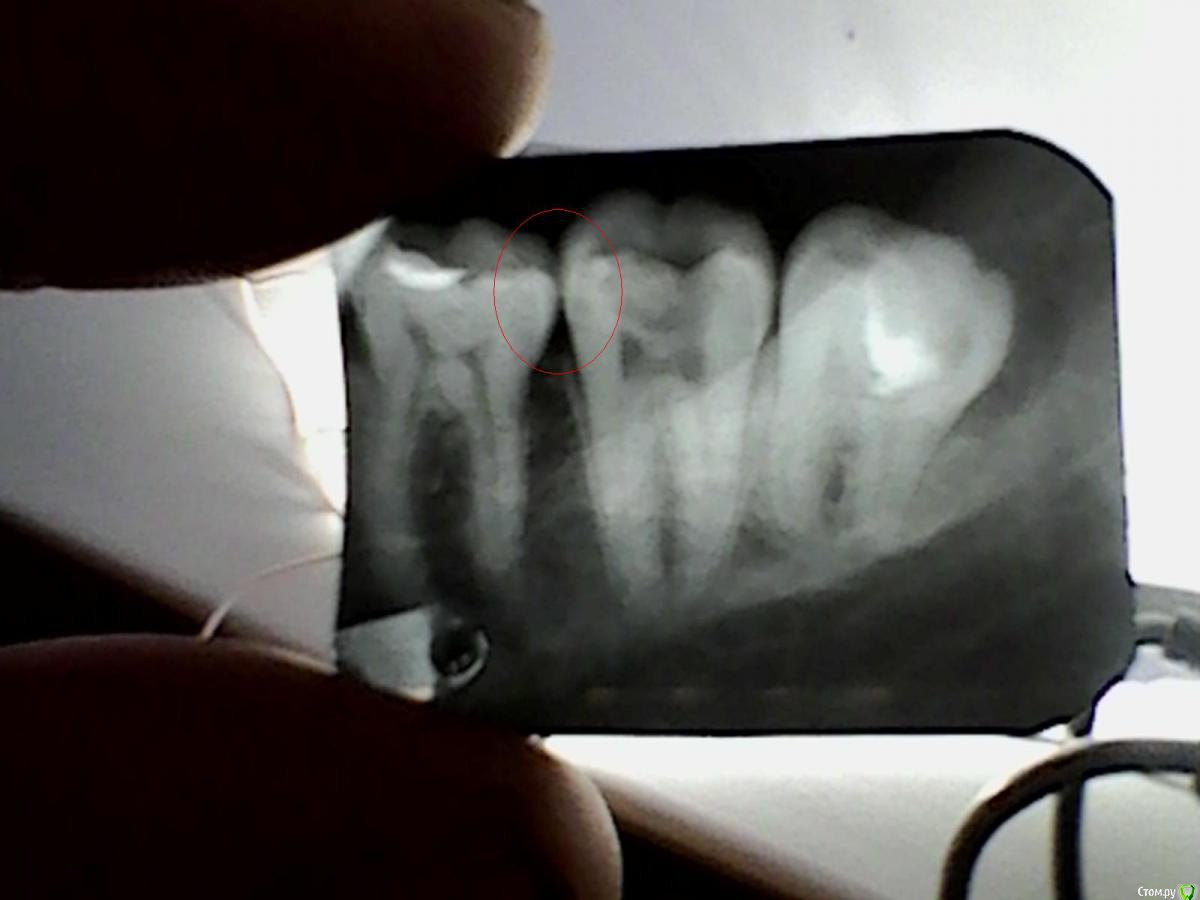

Гарриевич Опубликовано 5 апреля, 2015 Поделиться Опубликовано 5 апреля, 2015 По снимку между 6 и 7 никакой патологии нет. Не отмечали там застревание пищи? Ссылка на комментарий

SAnet Опубликовано 27 апреля, 2015 Автор Поделиться Опубликовано 27 апреля, 2015 Уважаемы врачи) а вы по этому снимку подозрительного не чего не видите?) на счет 8... сидит тихо.мне ее и обстучали, и воды лили тишина. По снимку я обозначил где примерно боли, тоже самое ближе к 5. Ссылка на комментарий